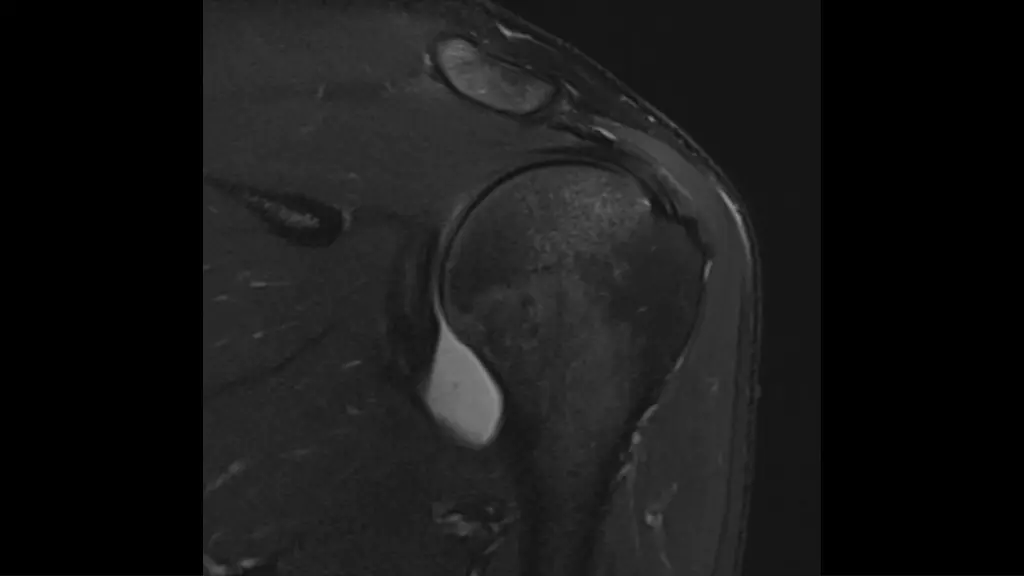

1. M31, M31, recurrent recurrent shoulder shoulder dislocation dislocation, last time , last time one one week week ago ago